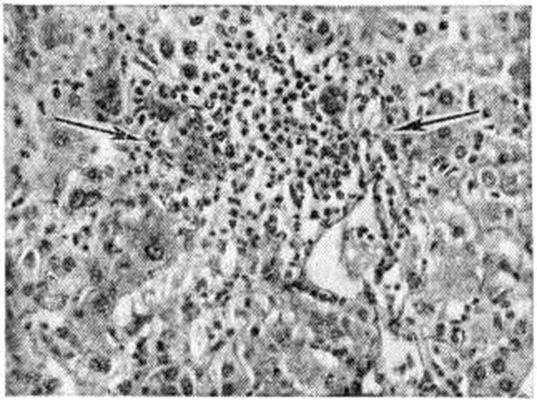

Рис. 4.

Микропрепарат печени при остром вирусном гепатите (пункционная биопсия): отёк и воспалительный инфильтрат в области центральной вены дольки печени (указано стрелками), проникающий в прилежащую паренхиму; окраска гематоксилин-эозином; × 300

При остром Гепатит вирусный морфологически изменения в продромальном периоде возникают за 1 — 7 дней до появления первых клин, признаков болезни и начинаются с активации и размножения звездчатых ретикулоэндотелиоцитов (купферовских клеток), а так-же эндотелия терминальных печёночных коллекторов, в зоне перехода синусоидного участка капилляров ацинуса в постсинусоидный — венозный. Вокруг терминальных печёночных коллекторов — периваскулярная инфильтрация из полиморфных мононуклеарных клеток (рисунок 4). В портальных трактах развивается отёк и обильная инфильтрация мононуклеарными клетками, напоминающими атипичные лимфоидные клетки или ретикулярные гистиоциты с небольшой примесью плазматических клеток. Возникает диффузная пролиферативная реакция купферовских клеток с образованием свободных клеточных форм. Часть купферовских клеток подвергается коагуляционному некрозу (смотри). В конце продромального периода присоединяются изменения гепатоцитов: анизонуклеоз с увеличением размеров ядрышек и преобладанием крупных ядер, многочисленные, главным образом патологический, митозы в различных зонах паренхимы, рассеянные белковые дистрофические изменения, преимущественно в гепатоцитах периферической зоны ацинусов (третья зона ацинуса).

К началу клинического — желтушного периода болезни уже имеется выраженная патоморфологические картина. К ранее возникшим изменениям присоединяется вакуольная (баллонная) дистрофия и некрозы гепатоцитов с образованием эозинофильных телец, сходных с тельцами Каунсилмена (рисунок 5).